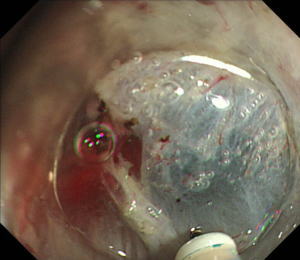

| 【胃ESD】 |

粘膜下層剥離術専用の電気メスを用いて早期胃癌のすぐ下の層(粘膜下層)を剥離します。 |